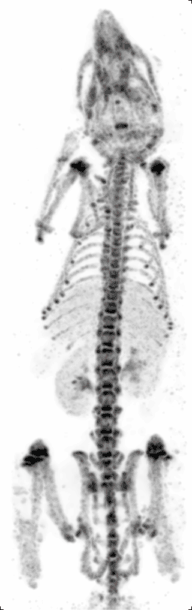

Micro-SPECT

Principle: Similar to PET, single photon emission computed tomography (SPECT) also images living systems through γ-rays emitted from within the subject. Unlike PET, the radioisotopes used in SPECT (such as technetium-99m) emit γ-rays directly,[10] instead of from annihilation events of a positron and electron. These rays are then captured by a γ-camera rotated around the subject and subsequently rendered into images.

Strengths: The benefit of this approach is that the nuclear isotopes are much more readily available, cheaper, and have longer half-lives as compared to micro-PET isotopes. Like micro-PET, micro-SPECT also has very good sensitivity and only nanograms of molecular probes are needed.[17] Furthermore, by using different energy radioisotopes conjugated to different molecular targets, micro-SPECT has the advantage over micro-PET in being able to image several molecular events simultaneously. At the same time, unlike micro-PET, micro-SPECT can reach very high spatial resolution by exploring pinhole collimation principle (Beekman et al.)[18] In this approach, by placing the object (e.g. rodent) close to the aperture of the pinhole, one can reach high magnification of its projection on detector surface and effectively compensate for intrinsic resolution of the crystal.

Weaknesses: Micro-SPECT still has considerable radiation which may affect physiological and immunological pathways in the small animals. Also, radiation may affect tumor size in cancer models as it mimics radiotherapy, and thus extra control groups might be needed to account for this potential confounding variable. Micro-SPECT can also be up to two orders of magnitude less sensitive than PET.[2] Furthermore, labeling compounds with micro-SPECT isotopes require chelating molarities which may alter their biochemical or physical properties.

Cancer research: Micro-SPECT is often used in cancer research for molecular imaging of cancer-specific ligands. It can also be used to image the brain because of its penetration power. Since newer radioisotopes involve nanoparticles such as 99mTC-labelled iron oxide nanoparticles, they could potentially be combined with drug delivery systems in the future.[16]